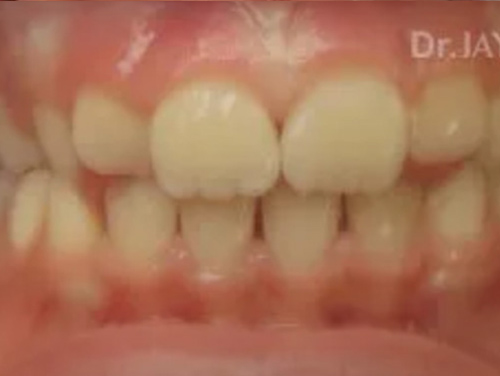

Severe crowding , parent had gone for a consult with 4 Orthodontist to resolve crowding. Orthodontist recommended extraction of multiple teeth to resolve crowding and straighten teeth. At Dr.Jay Dental , Dr. Jay finished the case with no extractions of teeth and just expansion of upper and lower jaws to accommodate all teeth.

Before

After